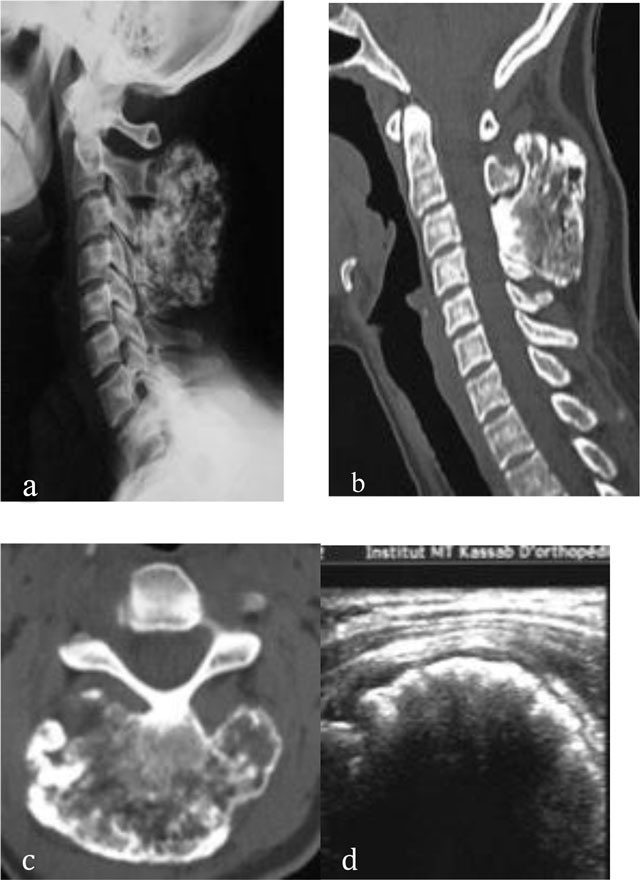

Figure 4

Osteochondroma of the cervical spine. Radiograph (a) shows an osseous mass located in the spinous processes of C3 and C4. CT scan (b, c) shows continuity of the osteochondroma with the spinous processes of C3 and C4. US (d) demonstrates a thin cartilaginous cap.